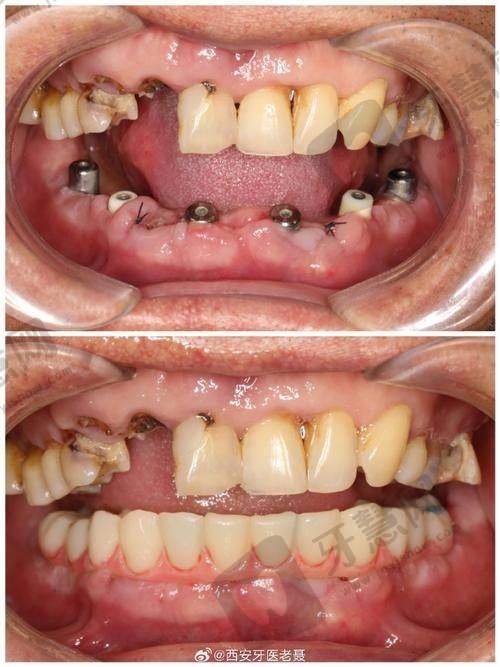

牙齿种植优势:牙齿种植科室拥有经验多的医生团队,能够熟练运用各种种植技术,为缺失牙患者提供稳固、美观的种植修复方案。

牙齿种植优势:牙齿种植项目采用国内外精良的种植系统,具有种植成功几率高、稳定性好等优点。医生会根据患者的口腔情况和需求,选择合适的种植体,为患者打造个性化的种植方案。

顾客B实例:“我因为牙齿缺失来这里做种植牙。医生的技术非常不错,种植过程特别顺利,而且术后修复得也特别快。现在我的牙齿就像自己的真牙一样,吃饭也方便多了。这家门诊部的服务也良好,以后看牙就认准这里了!”